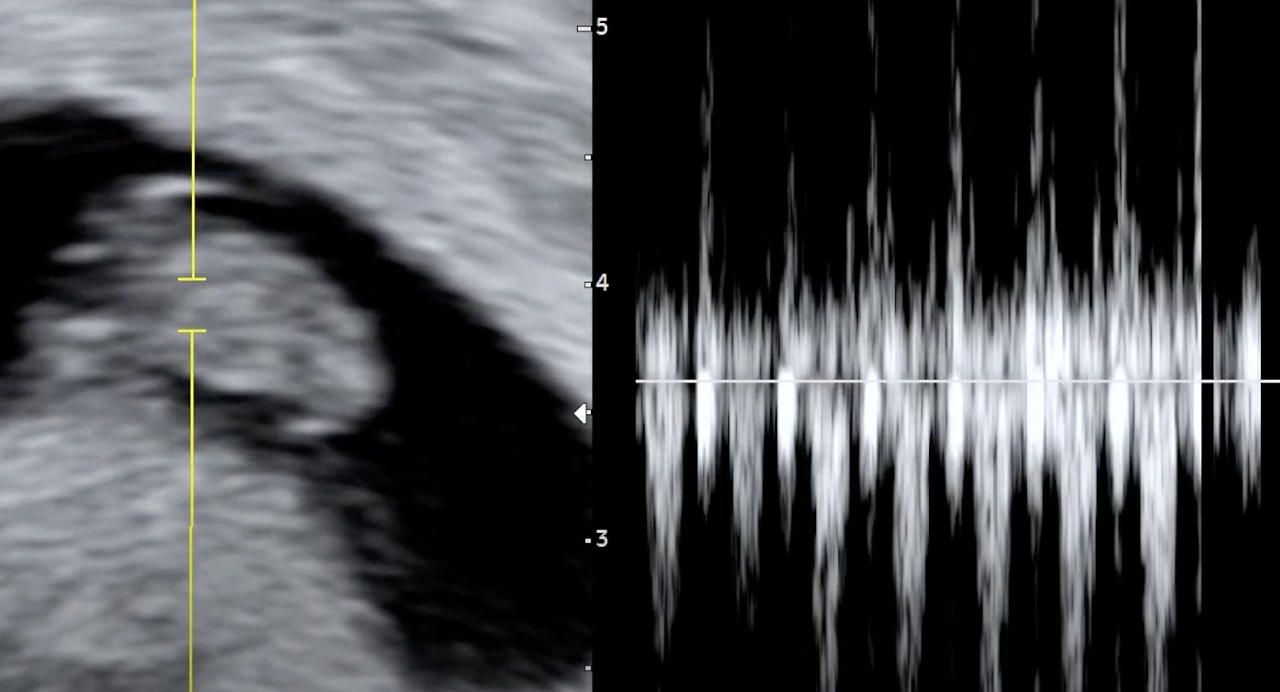

임신을 확인하고 2주 후. 두 번째 검진을 위해 산부인과로 향했다. 의사 선생님이 심장 소리를 들을 수 있을 거라 말씀하신 날이었다. 다행히 아기는 건강했다. 아기는 이제 키가 1.3cm가 넘었다. 약 9주부터 배아가 아니라 태아라고 부른다고 하니 아직 사람은 아닌 것인데, 나는 어서 빨리 사람이 되기를 기다린다.

아기는 아직 사람은 아니지만 2주 만에 심장이 생겼다. 건강히 잘 뛰고 있다. 진짜 아내에 배 안에 살아있는 생명이 있다. 평소 뛰는 줄 모르던 내 심장이 공명이라도 하는 듯 나댄다. 아기의 심장은 빠르게 뛴다. 심박수가 150 이 넘으니 내 심박수의 2배 정도다. 심장이 2배 빠르게 뛰는 만큼 아기의 시간은 나의 시간보다 두 배는 빠르게 흐를 거다. 여러 장기를 만들고 엄마의 태반과 연결될 준비를 하고, 팔과 다리를 만드느라 아주 바쁘다. 꼼꼼히 잘 만들어서 앞으로 100년은 튼튼하게 썼으면 좋겠다.